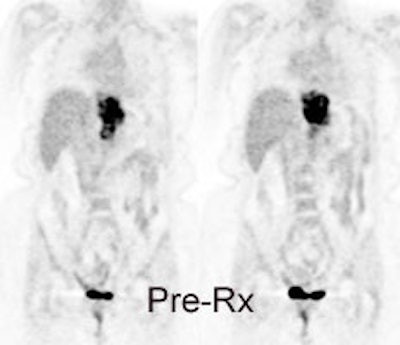

Response to therapy: This is the patient shown in the case above with progressive dysphagia and a large distal esophageal mass with gastrohepatic ligament adenopathy. Note the decreased uptake within the primary mass (arrowhead) and gastrohepatic nodes following initiation of radiation therapy. However, new uptake can be seen in two lymph nodes (black arrows) which were not identified prospectively on post-therapy CT imaging (white arrows on CT). The findings are concerning for metastatic disease and the patient went on to receive additional chemotherapy with subsequent resolution of the nodal uptake. |